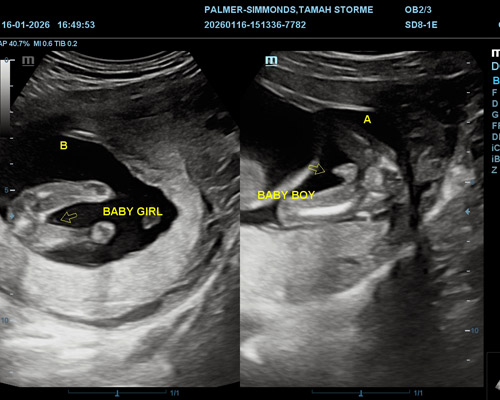

Gender determination in twin pregnancies is usually possible from around 15 weeks of pregnancy. At this stage, both babies are developed enough for the sonographer to identify their genders if their positions allow clear viewing.

- 2D ultrasound to determine your baby’s gender

Yes, a twin pregnancy gender scan can often determine the gender of both babies if their positions allow the sonographer to clearly see each baby during the ultrasound.

The genders of twins can usually be identified from around 15 weeks of pregnancy, when both babies are developed enough for clearer imaging.

If one baby’s position blocks the view, the sonographer may ask you to change position or continue scanning to try to identify the second baby’s gender.